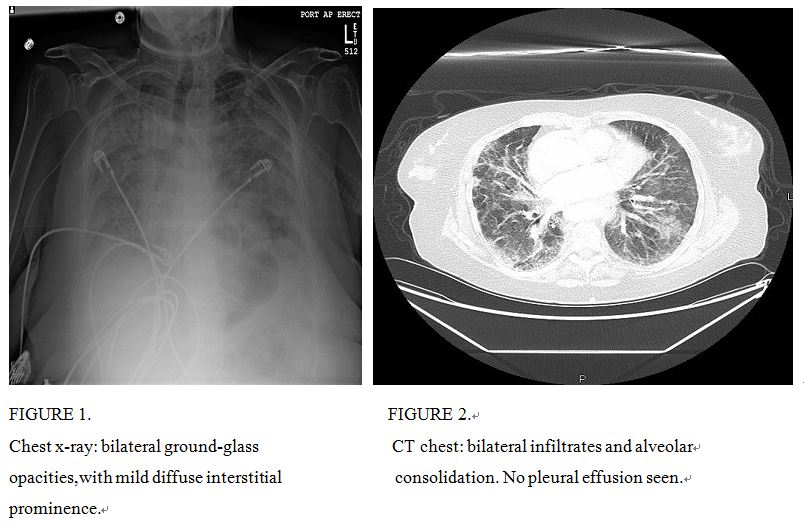

经过2次血液透析后的住院第3d的清晨,患者出现了低氧性呼吸衰竭,在高流量吸氧的情况下氧饱和度为84%,血气分析显示: pH7.2,PCO293.6mmHg,100%面罩吸氧时PO2。实施气管插管治疗。胸部X光检查(图1)示双肺毛玻璃样混浊,轻度弥漫性间质性改变。胸部CT显示双肺渗出和肺泡实变。通气/灌流扫描不支持肺栓塞。 铊和镓扫描呈阴性无任何病灶。心脏超声心动图显示右心室收缩压65-70mmHg,肺动脉扩张; 左心室射血分数为55%,肺动脉压62mmHg,而右动脉压力为100mmHg。按ARDSnet治疗方案要求继续进行低潮气量通气。5d后患者成功拔管,但患者表现出不说话且反应迟钝,开始使用抗精神病药物治疗,逐渐改善她的精神状态。复查胸部 X线片显示双肺渗出减少。10d后出院回家,到目前为止患者没有再出现锂中毒的症状。